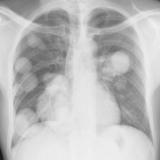

Mets

Album: Mets

Date: 02/18/2006

Size: 52 items

Views: 39820